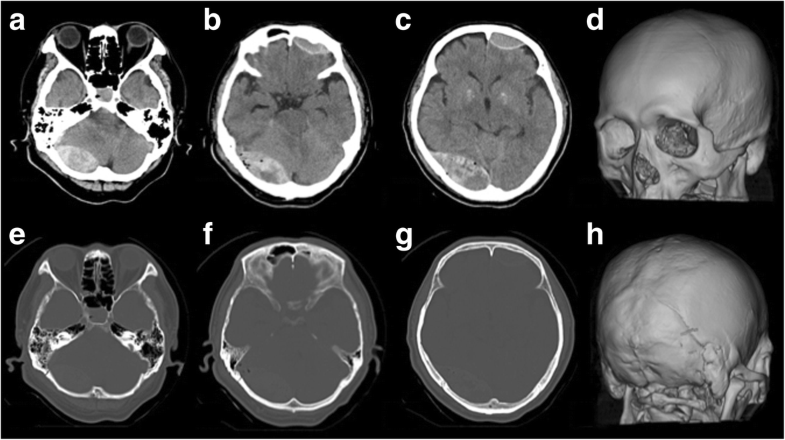

Skull Fracture with Parenchymal and Subdural Brain Hematomas

Skull Fracture with Parenchymal and Subdural Brain Hematomas from anatomicaljustice.com